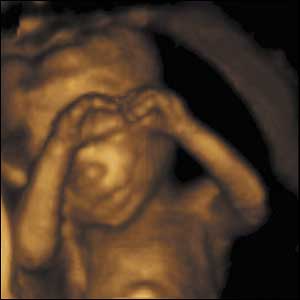

27 týdnů, 24 cm

Od 24 týdne je vyvinutá sítnice, děti mohou otevírat a zavírat oči a nacvičí si mrkací reflex, který jim pomůže chránit oči po narození.